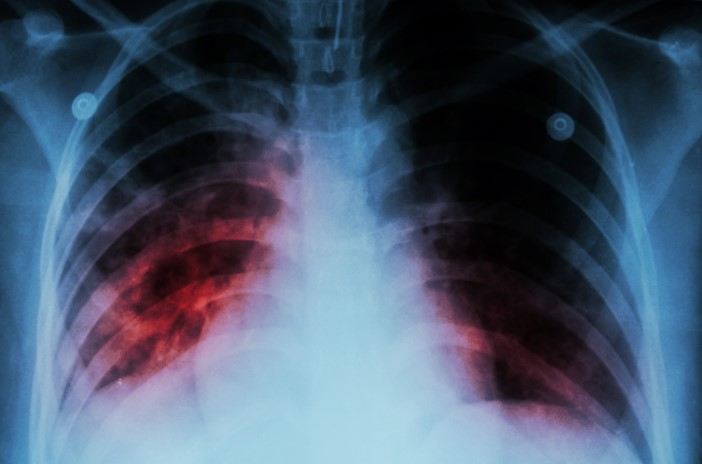

Ötən il 198 uşaq və yeniyetmə vərəmə yoluxub

Ötən il 198 uşaq və yeniyetmə vərəm xəstəliyinə yoluxub.

Sitat.info xəbər verir ki, bunu Səhiyyə Nazirliyi Elmi Tədqiqat Ağciyər Xəstəlikləri İnstitutunun direktoru İradə Axundova deyib.

O bildirib ki, 2024-cü il üçün bu göstərici 278 olub.

"2015-ci ildə hər 100 min nəfərə düşən vərəmlə xəstələnmə göstəricisi 41,1 olduğu halda, 2025-ci ildə bu rəqəm 21,5-ə enib. Vərəm xəstələrinin təxminən üçdə ikisini kişilər, üçdə birini isə qadınlar təşkil edir. Xəstəliyin aşkarlanma səviyyəsi də əhəmiyyətli dərəcədə artıb. Belə ki, 2015-ci ildə bu göstərici 53 faiz olduğu halda, 2025-ci ildə 86 faizə çatıb”, deyə o bildirib.